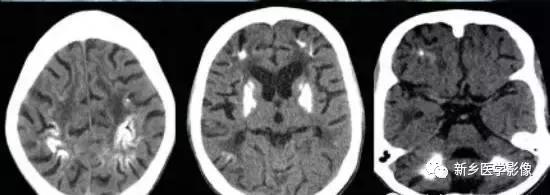

二、脑囊虫病

脑囊虫病慢性期,囊虫死亡以后,囊液逐渐被吸收,囊虫被机化,最后出现钙化。

钙化特点:多发、散在结节样钙化。钙化病灶通常较小、较圆、大小较均匀,少者单发或仅数个,多者可弥漫性分布于全部脑实质。